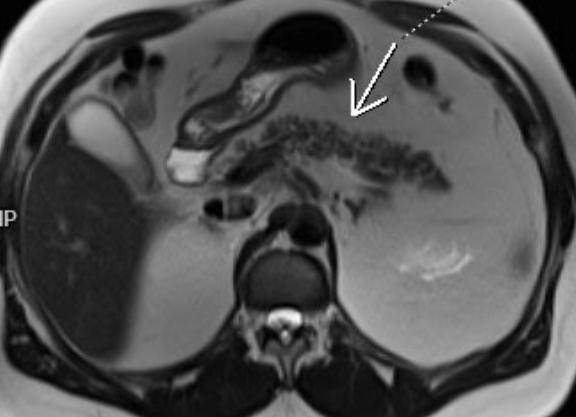

Магнитно-резонансная томография основана на возможности различных новообразований, развивающихся в паренхиматозных органах, с разной интенсивностью отражать магнитные волны. Естественно, качество снимков, которые будут выводиться на экран компьютера, обеспечивающего обработку изображений, будет зависеть от мощности используемого томографа. Чем мощнее аппарат, тем выше качество изображения и надежнее исследование.

Улучшить качество изображения можно также, применив специальные контрастные вещества. Контрастирование в комплексе с МРТ позволяет не только визуализировать самые мелкие изменения в органе, но и оценить состояние сосудов, которые его питают.

Исследование может показать мельчайшие изменения в структуре органа. Наиболее ценными считаются данные, полученные в случае, если у пациента во время проведения МРТ обнаружено объемное образование поджелудочной железы.

По результатам снимков определяют:

• положение и внутреннее строение органа;

• размеры головки, тела и хвоста железы;

• состояние парапанкреатической клетчатки;

• структуру паренхимы, присутствие патологических образований;

• плотность тканей патологии, что позволит отличить опухоль от кистозного образования;

• форму и размеры патологии, это поможет дифференцировать опухоль, ровные контуры и округлые формы говорят о доброкачественности образования;

• прорастание опухоли в окружающие ткани;

• метастазирование из других органов;

• состояние протоков, располагающихся внутри железы;

• присутствие в протоках камней;

• состояние сосудов, обеспечивающих питание органа и прочее.

Контрастирование применяют в основном когда необходимо подтвердить наличие в органе объемных новообразований. Раковые клетки задерживают контраст на более длительное время, тем самым обеспечивая улучшенную визуализацию опухоли.

Контрастирование при МРТ поджелудочной железы может использоваться также для диагностики патологий сосудов, питающих орган.